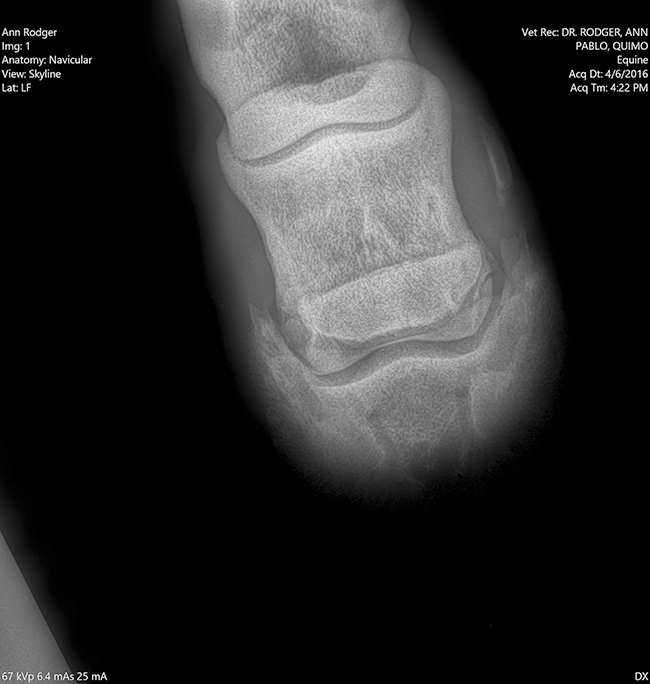

Radiología

Contamos con el equipo de radiología digital inalámbrico más avanzado del país, el cual permite obtener las mejores imágenes en el acto y compartirlas vía mail. Realiza radiografías de miembros, columna, cabeza, cuello y hombro.

Dra. Ann Rodger

Dr Ann Rodger Médica veterinaria egresado de la universidad de Bs.As. UBA

20 años de experiencia. Veterinaria FEI. A cargo de los caballos que participaron en Americano San Pablo 2008, Children Chile 2009, Juegos Panamericanos en Canadá 2015 y los Juegos Olímpicos Río 2016.

Veterinaria del concurso Haras El Capricho. Se especializó en UC Davis Universidad de California con el Dr. Jack Snyder; en Palm Beach con el Dr. John Steel; Mid Atlantic Equine Medical Center, New Jersey.